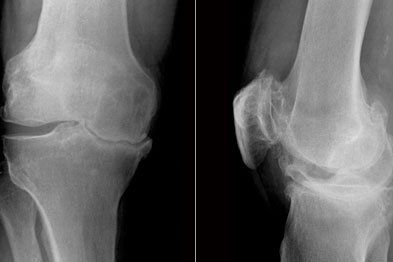

Diagnosis

There are a number of special tests that we can use to help diagnosis a meniscal injury and while the sensitivity and specificity of such tests are varied, a thorough understanding of the mechanism of injury and a cluster of these tests being positive, we can be confident in our diagnosis.